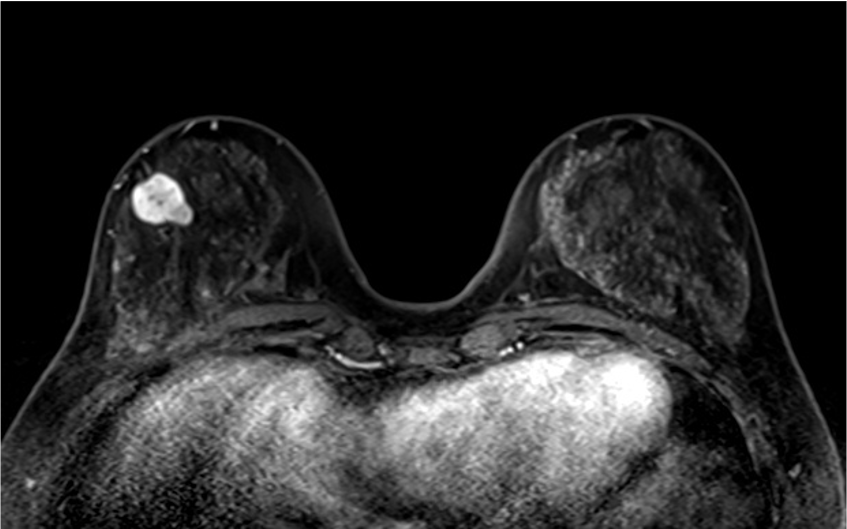

4. ダイナミックMRI (造影前 早期相 遅延相)

早期相で、乳腺の辺縁にBPE(矢印)を認めるが、その範囲は広くなくmildと判定する。乳癌の病変は、早期相から急速に造影され、遅延相でwash outがみられる。BPEは、遅延相で拡大し増強している。